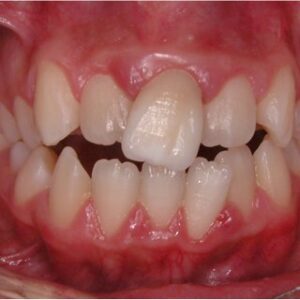

- شلوغی دندانی: دندانها به خاطر کمبود جا روی هم قرار میگیرند

- کراسبایت: دندانهای عقبی فک بالا به فک پایین منتقل میشوند

زمانی که بحث درمان تنگی بالا مطرح میشود تنها به فکر بازگرداندن زیبایی نیستیم، بلکه در غیر اینصورت مجموعهای از مشکلات عملکردی ممکن است فرد را تهدید کند. برای مثال از نظر دندانی، کراس بایت و تنگی فک بالا ساییدگی ناهموار دندانها و جویدن سختتر را میکند و در نتیجه هضم را مختل میکند. درمان شلوغی دندان بیشتر نیاز به وسیع کردن اولیه دارد، به همین دلیل ارتودنسی به تنهایی جواب نمیدهد.